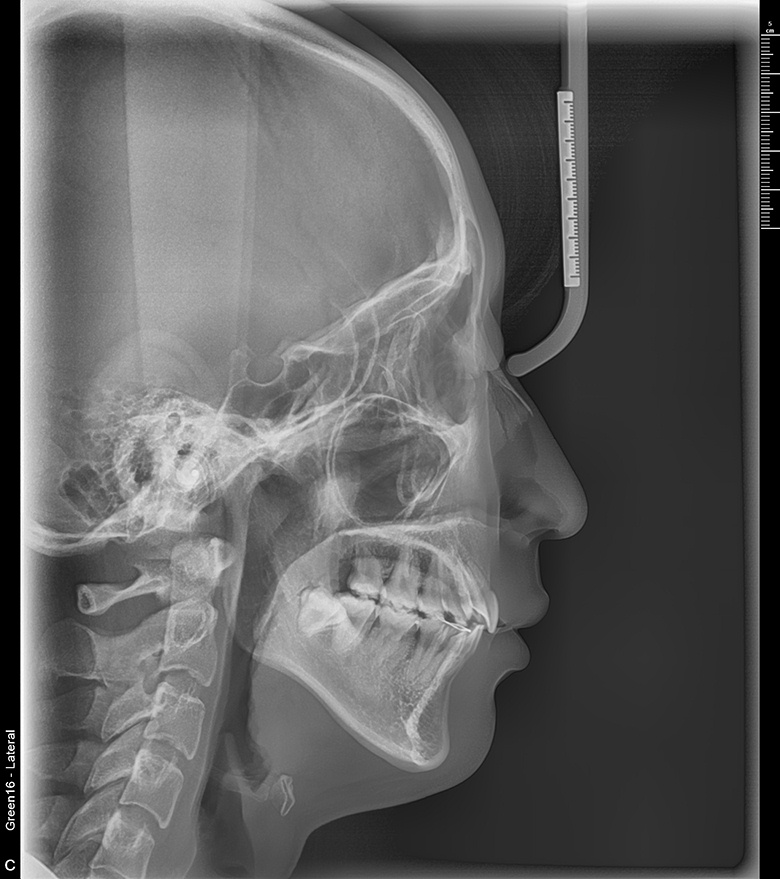

치료 후 사진입니다.